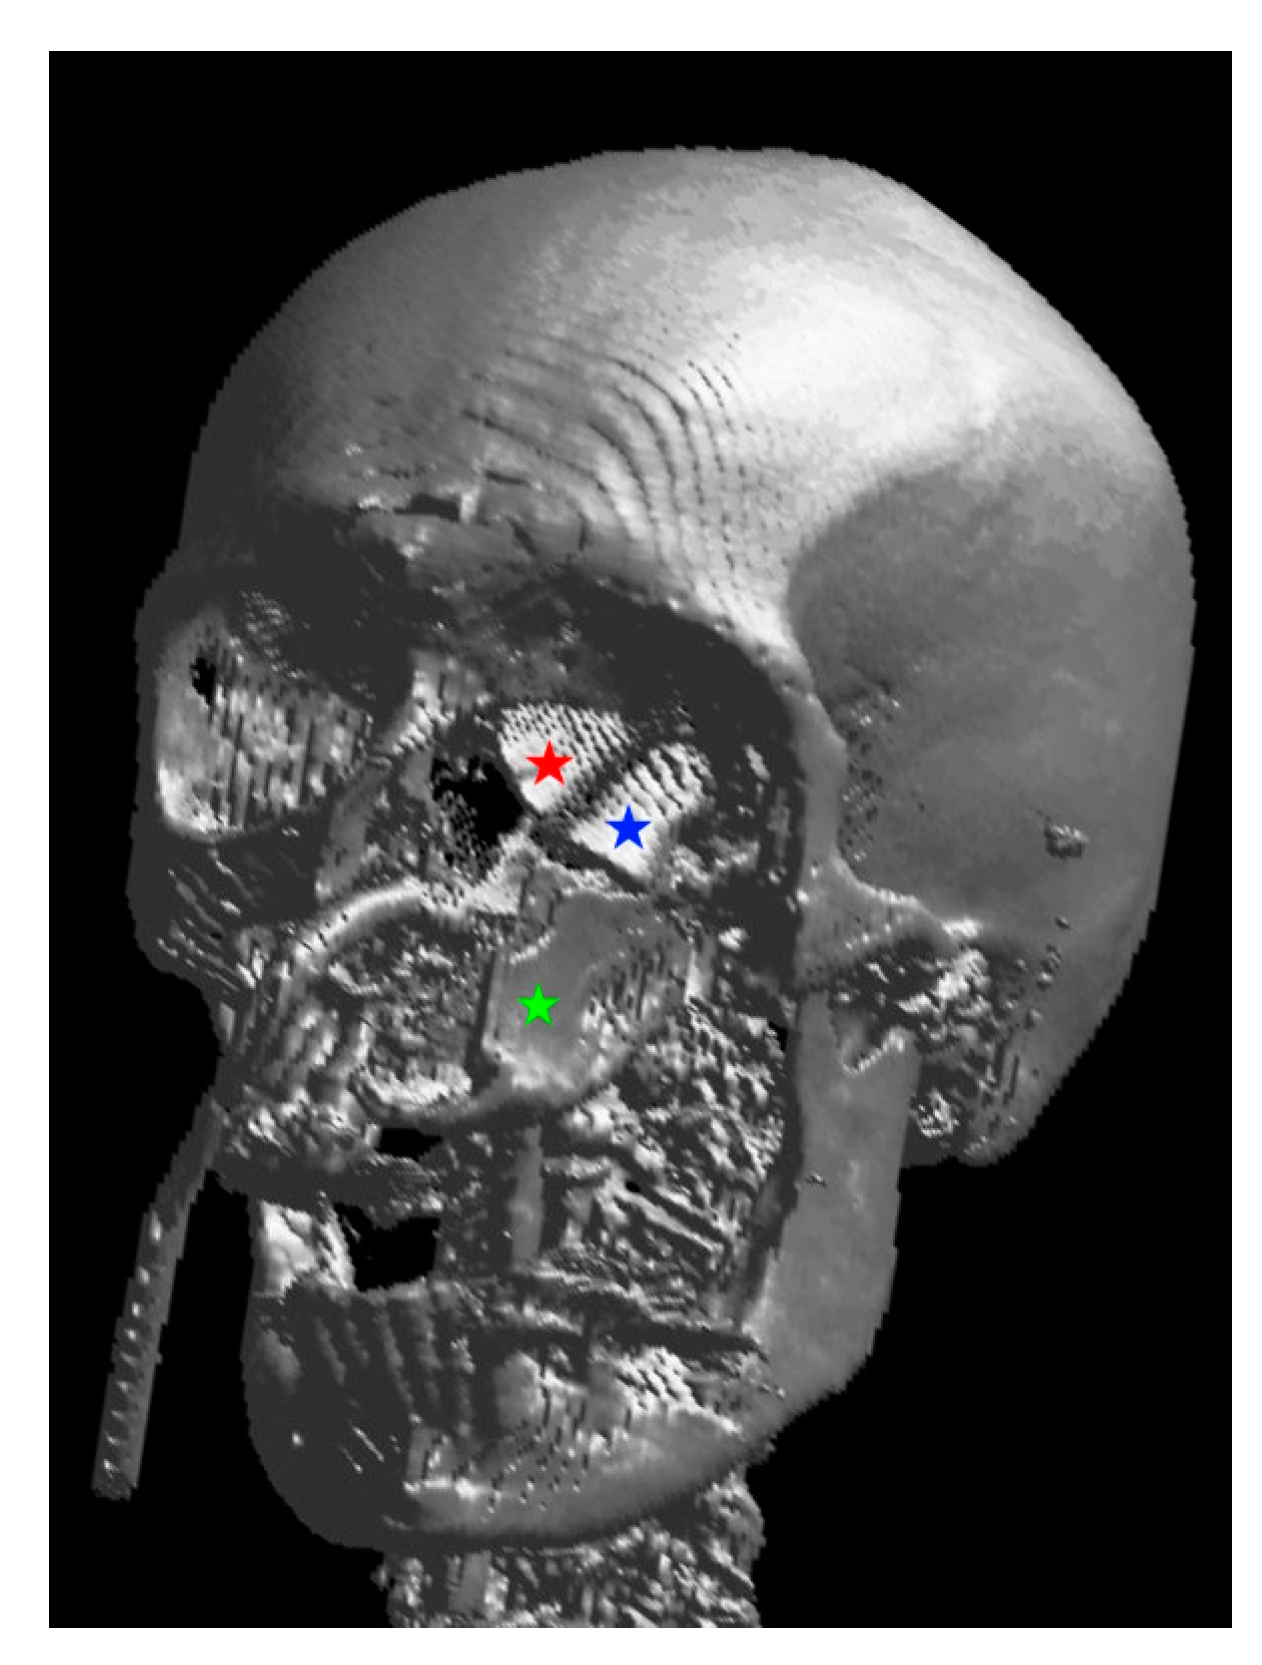

Figure 3. Three-dimensional rendering of the reconstruction: the red star marks the neo-medial wall, the blue star the neo-orbital floor, both belong to the MFC flap, and the green star marks the vertically oriented DCIA flap.